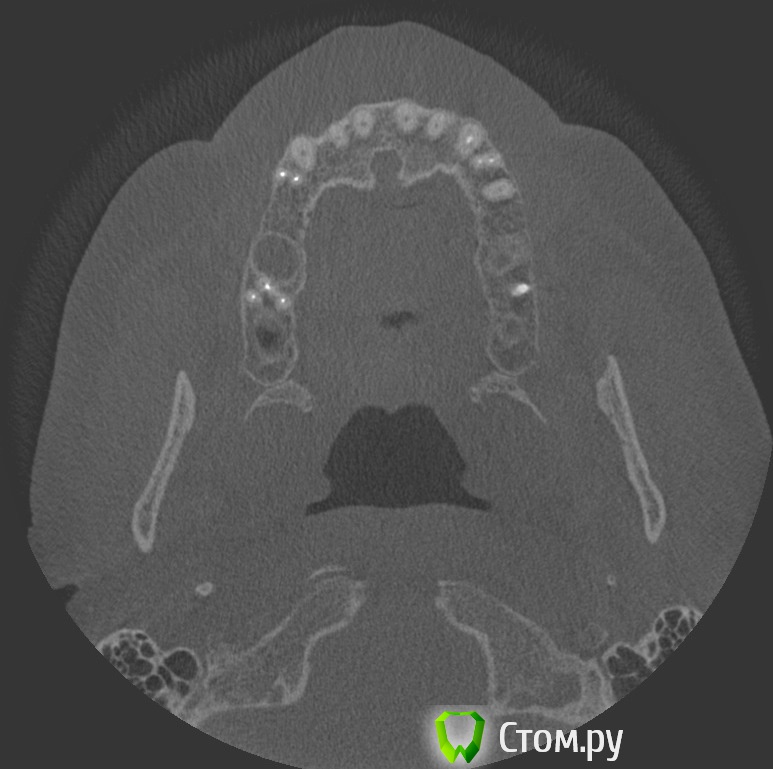

dr-krasnov Опубликовано 10 июня, 2014 Поделиться Опубликовано 10 июня, 2014 Добрый день. На томограмме ретенционная киста слева, одонтогенный синусит справа, замыкательная кортикальная пластина в области корня уже отсутствует. (желтые стрелки) С моей точки зрения необходимо эндоперелечивание причинного зуба. К лору можно сходить за рекомендациями по поводу ретенционной кисты. Обычно с ними ничего не делают, пока они не беспокоят. 1 Ссылка на комментарий

dr-krasnov Опубликовано 10 июня, 2014 Поделиться Опубликовано 10 июня, 2014 (изменено) Тэкс, посмотрел КТ. Претензий к лечению зуба не имею. 4й канал найти не удалось. То был ограниченный артефакт от запломбированного канала. Связи между этим зубом и реакцией слизистой скорее всего нет. Да и синусита нет. Изменения слизистой скорее имеют гиперпластическую природу. Источником исходных реакций послужили уже отсутствующие зубы. Архивные снимки расставили бы все точки над и. Несколько картинок: Небный на осях, можно придраться к незначительному расширению периодонтального пространства апикально, но я бы не стал http://s018.radikal.ru/i515/1406/b8/d712dd4f6158.jpg Дистальный щечный http://s020.radikal.ru/i710/1406/4f/990608ed482a.jpg Мезиальный щечный http://s018.radikal.ru/i518/1406/52/534d8d8534ec.jpg В общем, признаков периодонтита не вижу, рентгенологических показаний для резекции тоже.Я бы порекомендовал динамическое наблюдение. Изменено 10 июня, 2014 пользователем dr-krasnov 1 Ссылка на комментарий